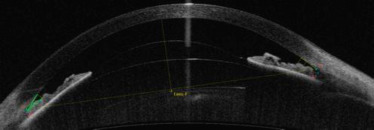

Depuis l'avènement du SS-OCT, la rapidité d'analyse permet la reconstitution du profil cornéen pour la représentation en topographie d'élévation [ 25 ]. Ainsi, la tomographie OCT vise à supplanter la traditionnelle tomographie par balayage en fente optique ou par rotation de type Scheimpflug. Elle a une plus grande efficience pour passer à travers des milieux de transparence réduite tout en conservant une résolution spatiale comparable ( fig. 3-21

Fig. 3-21

Représentation de la cartographie cornéenne en mode élévation obtenue par SS-OCT.Les élévations antérieures et postérieures sont définies par rapport à une surface de référence préétablie.